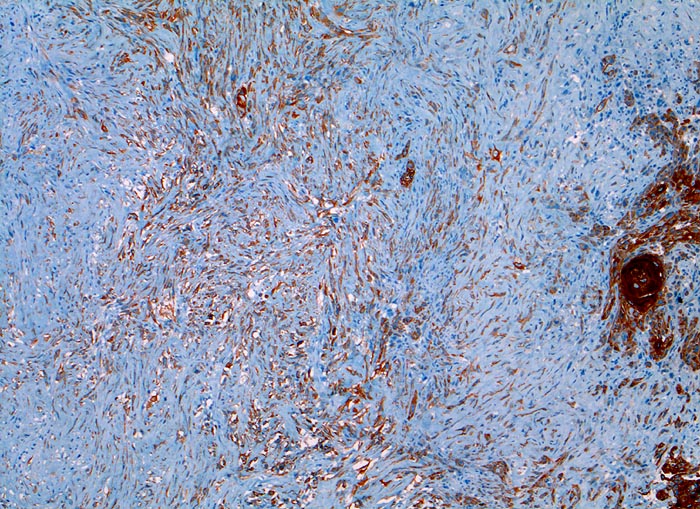

Diagnostischer Nutzen:

Suchantikörper zur Abgrenzung von Karzinomen von Lymphomen, Sarkomen und malignen Melanomen. Identifikation von Karzinommikrometastasen in Lymphknoten.